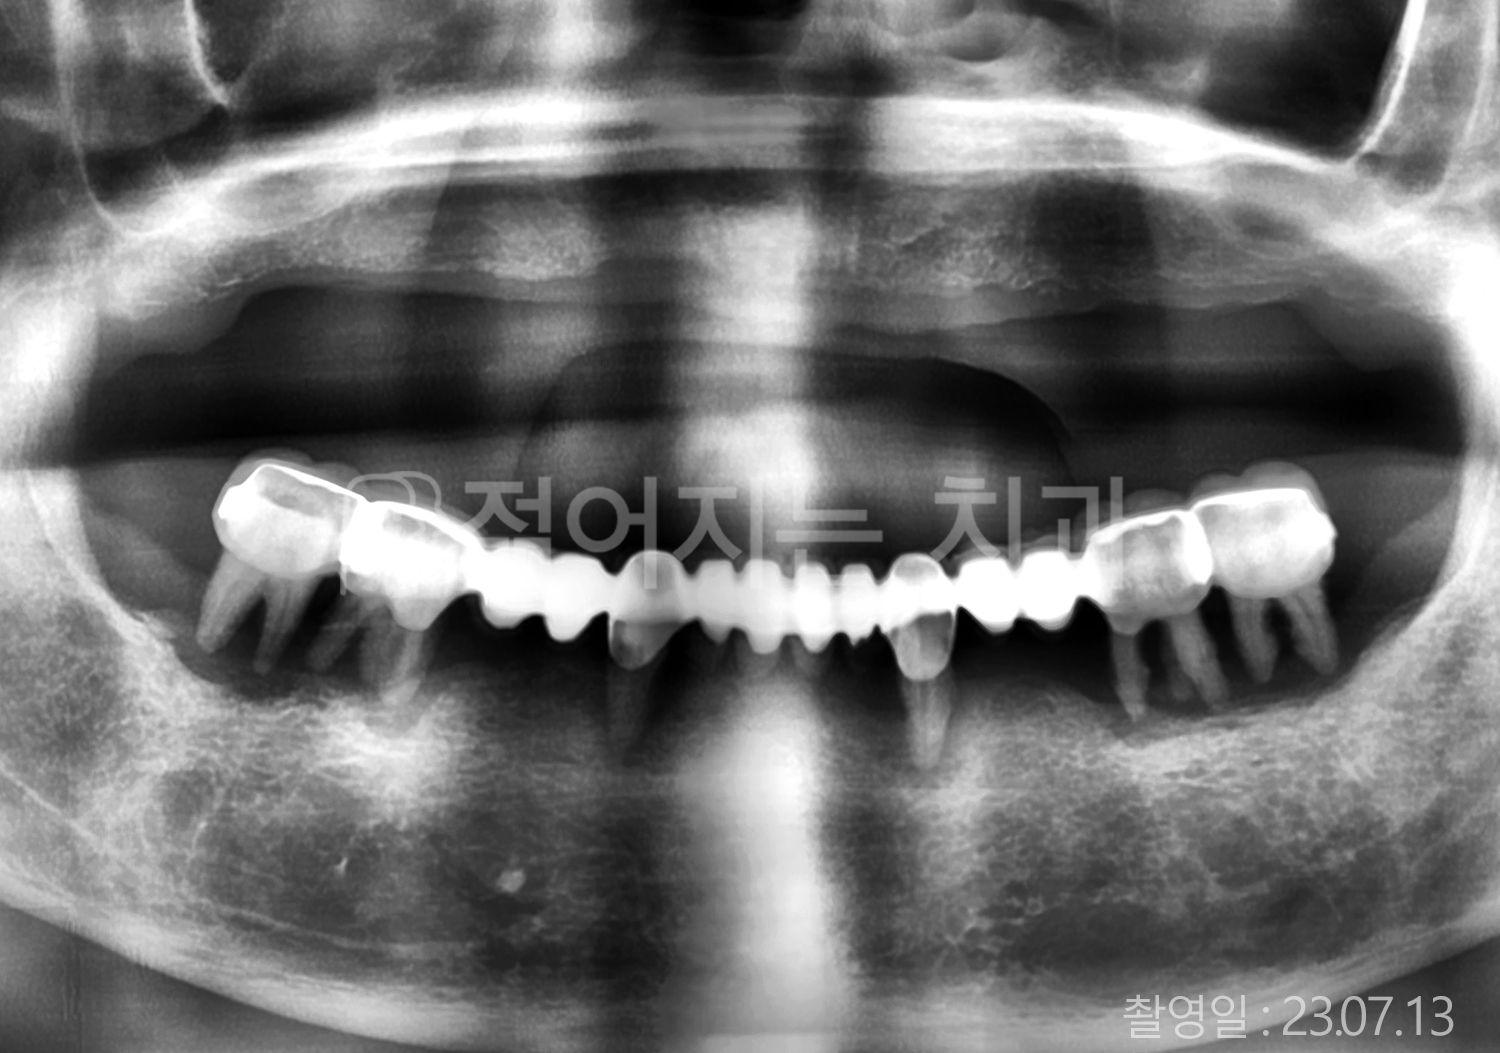

• 70대 고혈압, 당뇨 전체치아 10개 이상 임플란트

• 50대 고혈압, 당뇨 전체치아 10개 이상 임플란트

• 60대 고혈압, 당뇨 전체치아 10개 이상 임플란트

• 50대 전체치아 10개 이상 임플란트

• 70대 당뇨 전체치아 10개 이상 임플란트

• 80대 전체치아 10개 이상 임플란트

• 40대 전체치아 10개 이상 임플란트

• 60대 고협압, 고지혈증 전체치아 10개 이상 임플란트

• 60대 전체치아 10개 이상 임플란트